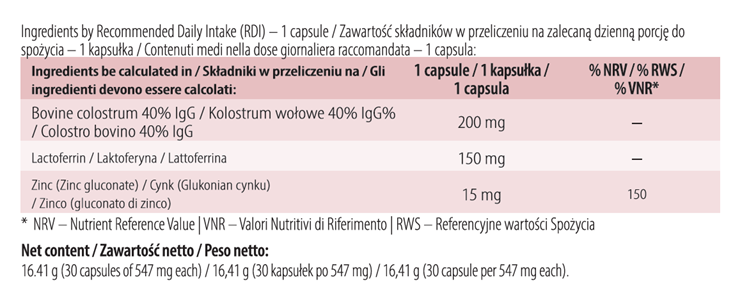

Collaceina Immune is a combination of high dose of colostrum, lactoferrin and zinc.

Colostrum standardised to 40% immunoglobulins means that 40% of its composition are immunoglobulins, i.e. proteins of the immune system. Such standardisation ensures a consistent amount in each dose.

Ingredients: Beef milk colostrum (40% IgG), milk lactoferrin, zinc (zinc gluconate), fish gelatin, bulking agent (microcrystalline cellulose), anti-caking agent (magnesium salts of fatty acids).

Recommended daily intake: 1 capsule. Take once daily, with food and plenty of water.